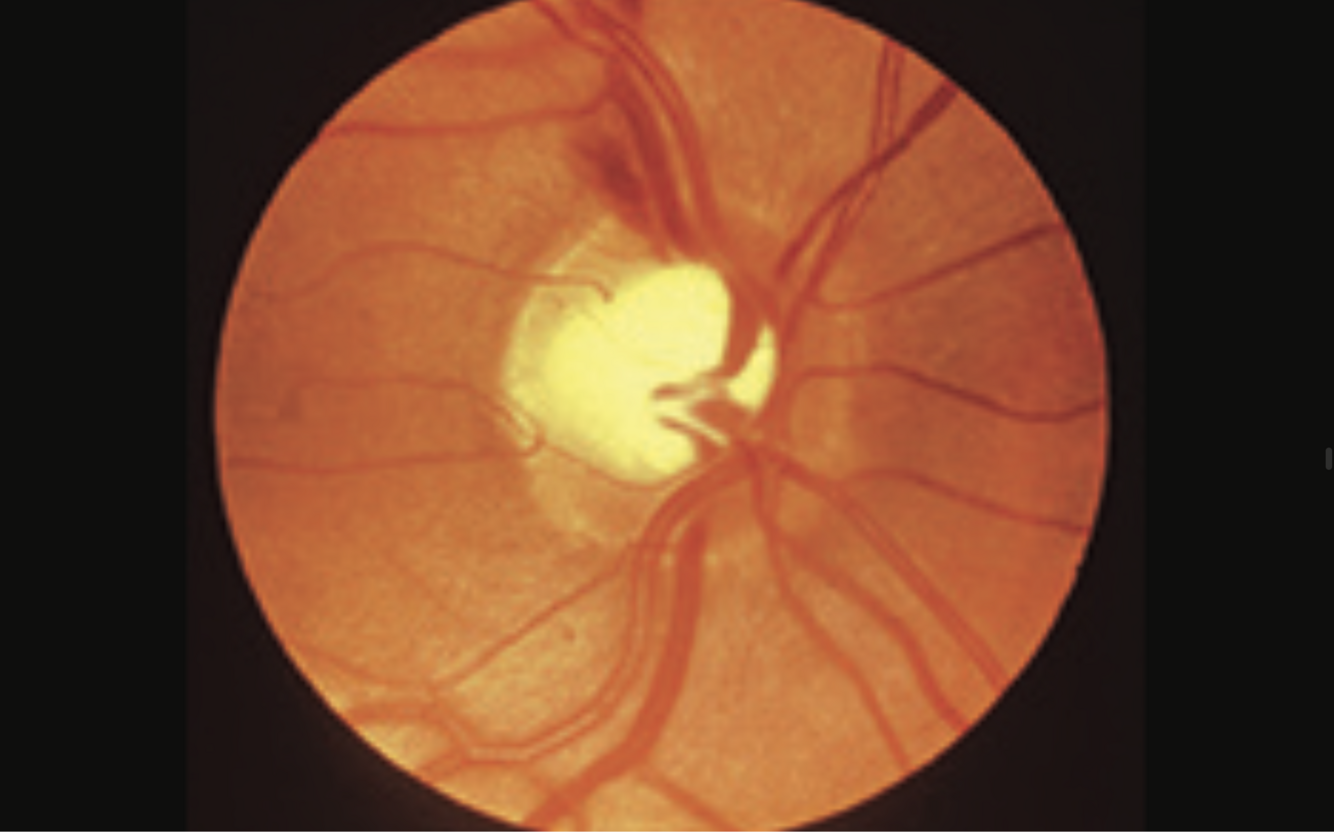

glaucoma

- large cup disc ratio >0.5 = optic disc cupping

- nasal displacement